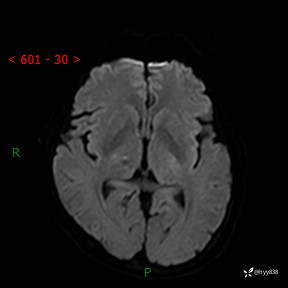

颅脑MRI平扫